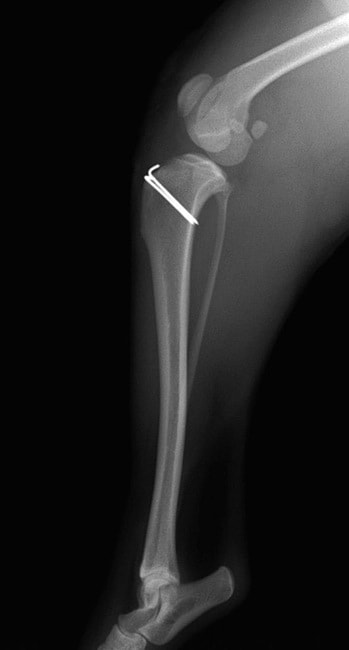

■ 症例20 ポメラニアン 8ヶ月 1.8kg

左右膝蓋骨脱臼 グレードⅢ

2ヶ月前から間欠的跛行が認められ、両膝の膝蓋骨脱臼整復術を行った。

手技は縫工筋及び内側広筋の解放、脛骨粗面の外側転位、滑車ブロック形造溝術、内外側関節包の縫縮を選択し実施した。

右側の膝蓋骨脱臼は上記手技で整復されたものの、左側はそれのみでは膝蓋骨が浮く様子が認められた。その為、PDS縫合糸にて膝蓋靱帯を1糸のみ縫合し、靱帯の縫縮を行った。

膝蓋骨脱臼は膝関節における膝蓋骨の内外側の脱臼と定義されるが、時として単純な内外の脱臼ではなく、膝蓋骨が大きく前方に浮き上がるように脱臼する場合がある。特にトイプードルやポメラニアンといった犬種に多く認められる。

内側脱臼に加えて前方への浮き上がりを矯正する為に、従来より脛骨粗面転移により膝蓋靭帯を外方と下方に引っ張り、固定する方法を選択する。膝蓋骨の前方への浮き上がりが軽度の場合は、従来法ではなく関節包の縫縮で対応していた。しかし、一部の症例で膝蓋骨の動きが悪くなり伸展機構が円滑に機能せずロボット様歩行になるケースがあった。

その為、膝蓋靭帯自体を縫縮する方法を採用した。この方法により、膝関節の伸展機構を妨げず膝蓋骨の軽度の浮きを矯正することが可能となった。

本症例の経過は良好である